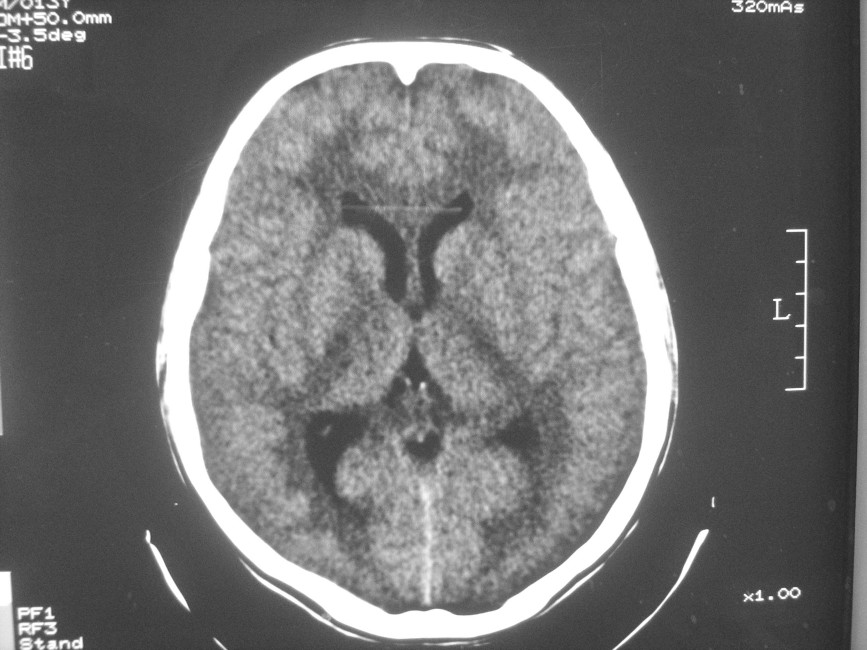

以下是引用zzyy在2008-6-16 10:13:00的发言:[br]两侧脑白质呈对称性密度减低,病儿有发热及脑膜刺激征。考虑急性病毒性脑炎。